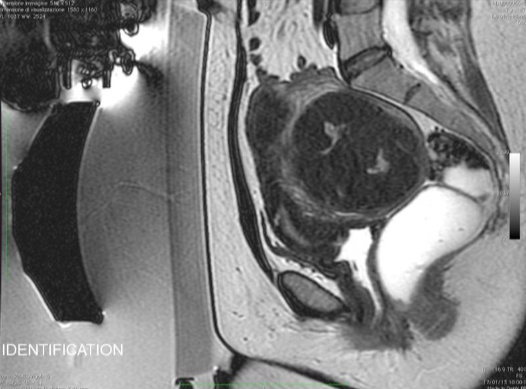

在开始该程序之前,会先进行手动分割操作。 随后,一款专用软件会自动制定出最佳的治疗方案。

在操作过程中,会进行多次超声波治疗,直至覆盖住足够的子宫肌瘤体积。 每次超声处理持续 20 至 40 秒,每次超声处理之间会有冷却时间(最长可达 90 秒)。 磁共振成像技术中质子共振频率的偏移特性使得能够监测每一个治疗点的温度。

经过治疗后,会进行核磁增强以评估被切除区域的范围。